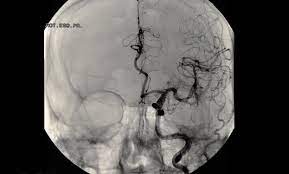

Kleines aneurysma im kopf. Ein Aneurysma vor allem im Gehirn kann angeboren sein. Häufig befinden sich die Aneurysmen im Kopf an den Aufzweigungen Bifurkationen der Arterien. Schließlich kann das Aneurysma platzen und eine unter Umständen lebensgefährliche Blutung im Kopf bewirken.

Ein Aneurysma vor allem im Gehirn kann angeboren sein. Da das Schiff beginnt sich aufzublähen wird es wahrscheinlicher zu platzen. Niemand kann vorhersagen wann ein Aneurysma platzt und Leck Blut in die umliegenden Gebiete. Solange ein Aneurysma noch klein und intakt ist das Gefäß also keine Risse hat verursacht es häufig keinerlei oder nur unspezifische Beschwerden wie Kopfschmerzen oder Übelkeit. Wenn ein Blutgefäß erweitert oder Ballons durch Schwächung Wände heißt es ein Aneurysma. Je nach Größe und Lage des Aneurysmas im Gehirn können jedoch auch Beschwerden auftreten. Ein Aneurysma ist eine krankhafte Aussackung einer Schlagader. Fachleute gehen aber davon aus dass Aneurysmen mit einem Durchmesser unter sieben Millimetern nicht sofort behandelt werden müssen sondern beobachtet werden können. Je nach Größe und Ort sind weitere Symptome möglich.

Nicht rupturierte intrakranielle Aneurysmen finden sich bei etwa drei Prozent der Erwachsenen. Ein Aneurysma ist eine krankhafte Gefäßausstülpung also eine örtlich begrenzte Erweiterung einer Arterie. Ein Aneurysma ist eine krankhafte Gefäßausstülpung die sich an den hirnversorgenden Gefäßen zumeist an Gefäßaufzweigungen befindet. Die meisten Gefäßaussackungen im Kopf entdecken Ärzte durch Zufall oder weil sie Symptome wie beispielsweise Doppeltsehen verursachen. Täglich im Kühlschrank aufbewahren. Aber es lässt sich nicht ganz ausschließen dass auch solche kleinen Aneurysmen reißen. Niemand kann vorhersagen wann ein Aneurysma platzt und Leck Blut in die umliegenden Gebiete.